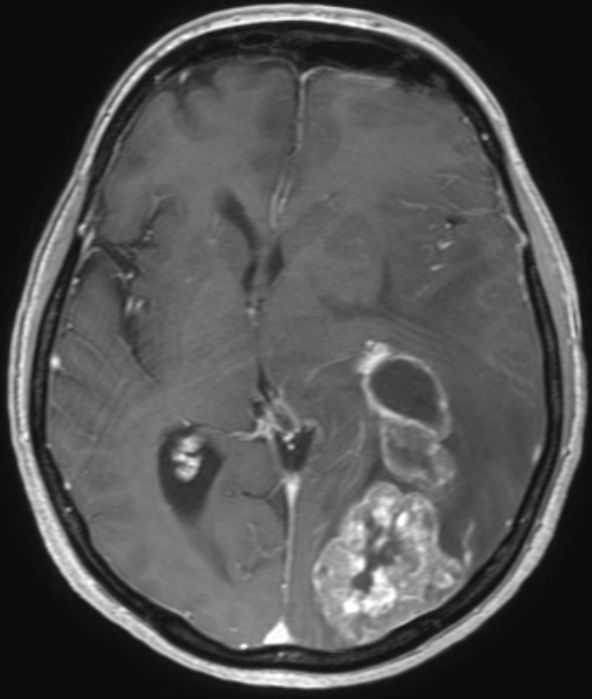

| Hirnmetastase | 48-jährige Frau, die vor 4 Jahren ein DLBCL Stadium IVa mit Bulk rechts inguinal, Lymphknoten mediastinal axillär links, Milzvergrößerung und pulmonale Infiltration hatte. 8mal R-CHOP, RT der rechts inguinalen Lymphknoten mit 26 Gy. Vor 5 Monaten Tumor linker Hilus und Hirnmetastase links occipito-parietal: Histologie: großzelliger neuroendokriner Tumor. Entfernung der Hirnmetastase, RT Neurocranium. 6 x Carboplatin/Etoposid: PR des Lungentumors, vitaler Resttumor des Gehirns | |||||||||||||||||||

MRT T1 FFE: Ausgedehnte Matastase li occipital.![]() | |||||||||||||||||||

MRT MIP T1 FFE![]() | |||||||||||||||||||

MRT MIP T1 FFE![]() |